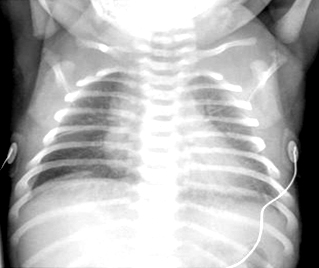

Taquipneia transitória do neonato (síndrome do desconforto respiratório tipo 2): estrias peri-hilares e fluido na fissura horizontal à direita

Do acervo de Ponthenkandath Sasidharan, MD; usado com permissão